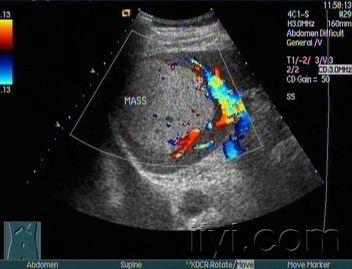

脾脏囊肿一例 - 超声医学讨论版 - 爱爱医医学论坛

脾下极实性肿块能确定是副脾吗?

【讨论】脾脏实性占位声像图 - 超声医学讨论版 - 医

副脾彩超图片

副脾的超声表现图片